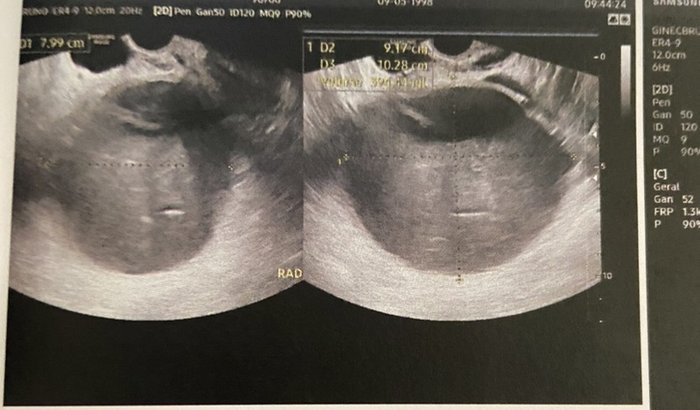

Oi. Eu sou a Duda. Recentemente eu senti muitas dores na parte inferior da barriga ao lado direto. Depois de alguns exames foi encontrado um cisto de 10cm no meu ovário, de característica hemorrágica.  De acordo com a médica que me atendeu esse cisto não pode sumir sozinho pois é grande demais, então ele só sai cirurgicamente.  A cirurgia foi avaliada em um valor de 7 a 8 mil reais, infelizmente o meu plano ainda não cobre esse tipo de cirurgia por ser um plano recente.  Pelo SUS a cirurgia demoraria mais de 90 dias para ser liberada, e nesse tempo o cisto pode romper, o que colocaria a minha vida em risco!  Peço a ajuda de vocês para que eu consiga realizar essa cirurgia!  Obrigada.  Atenciosamente, Duda!